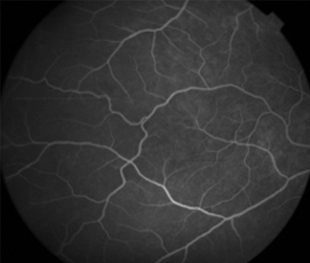

Angiografía OI

- Angiografía: teñido arterial, escape capilar, más tardíamente, no perfusion arteriolar y venular con teñido de las paredes vasculares y dilatación venosa.